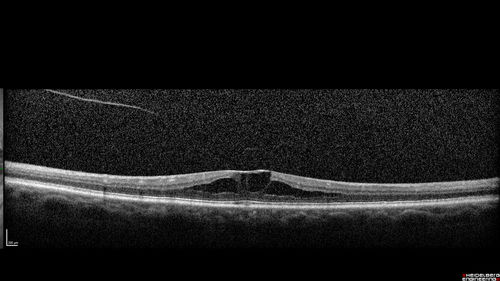

Stellate non-hereditary idiopathic foveomacular retinoschisis (SNIFR) and optic nerve drusen

84 year old man No visual complaints. Not diabetic, cataract surgery 8 years ago. Meds: Omeprazole, Tamsulosin (Flomax)

VA 20/32 OD, 20/20 OS